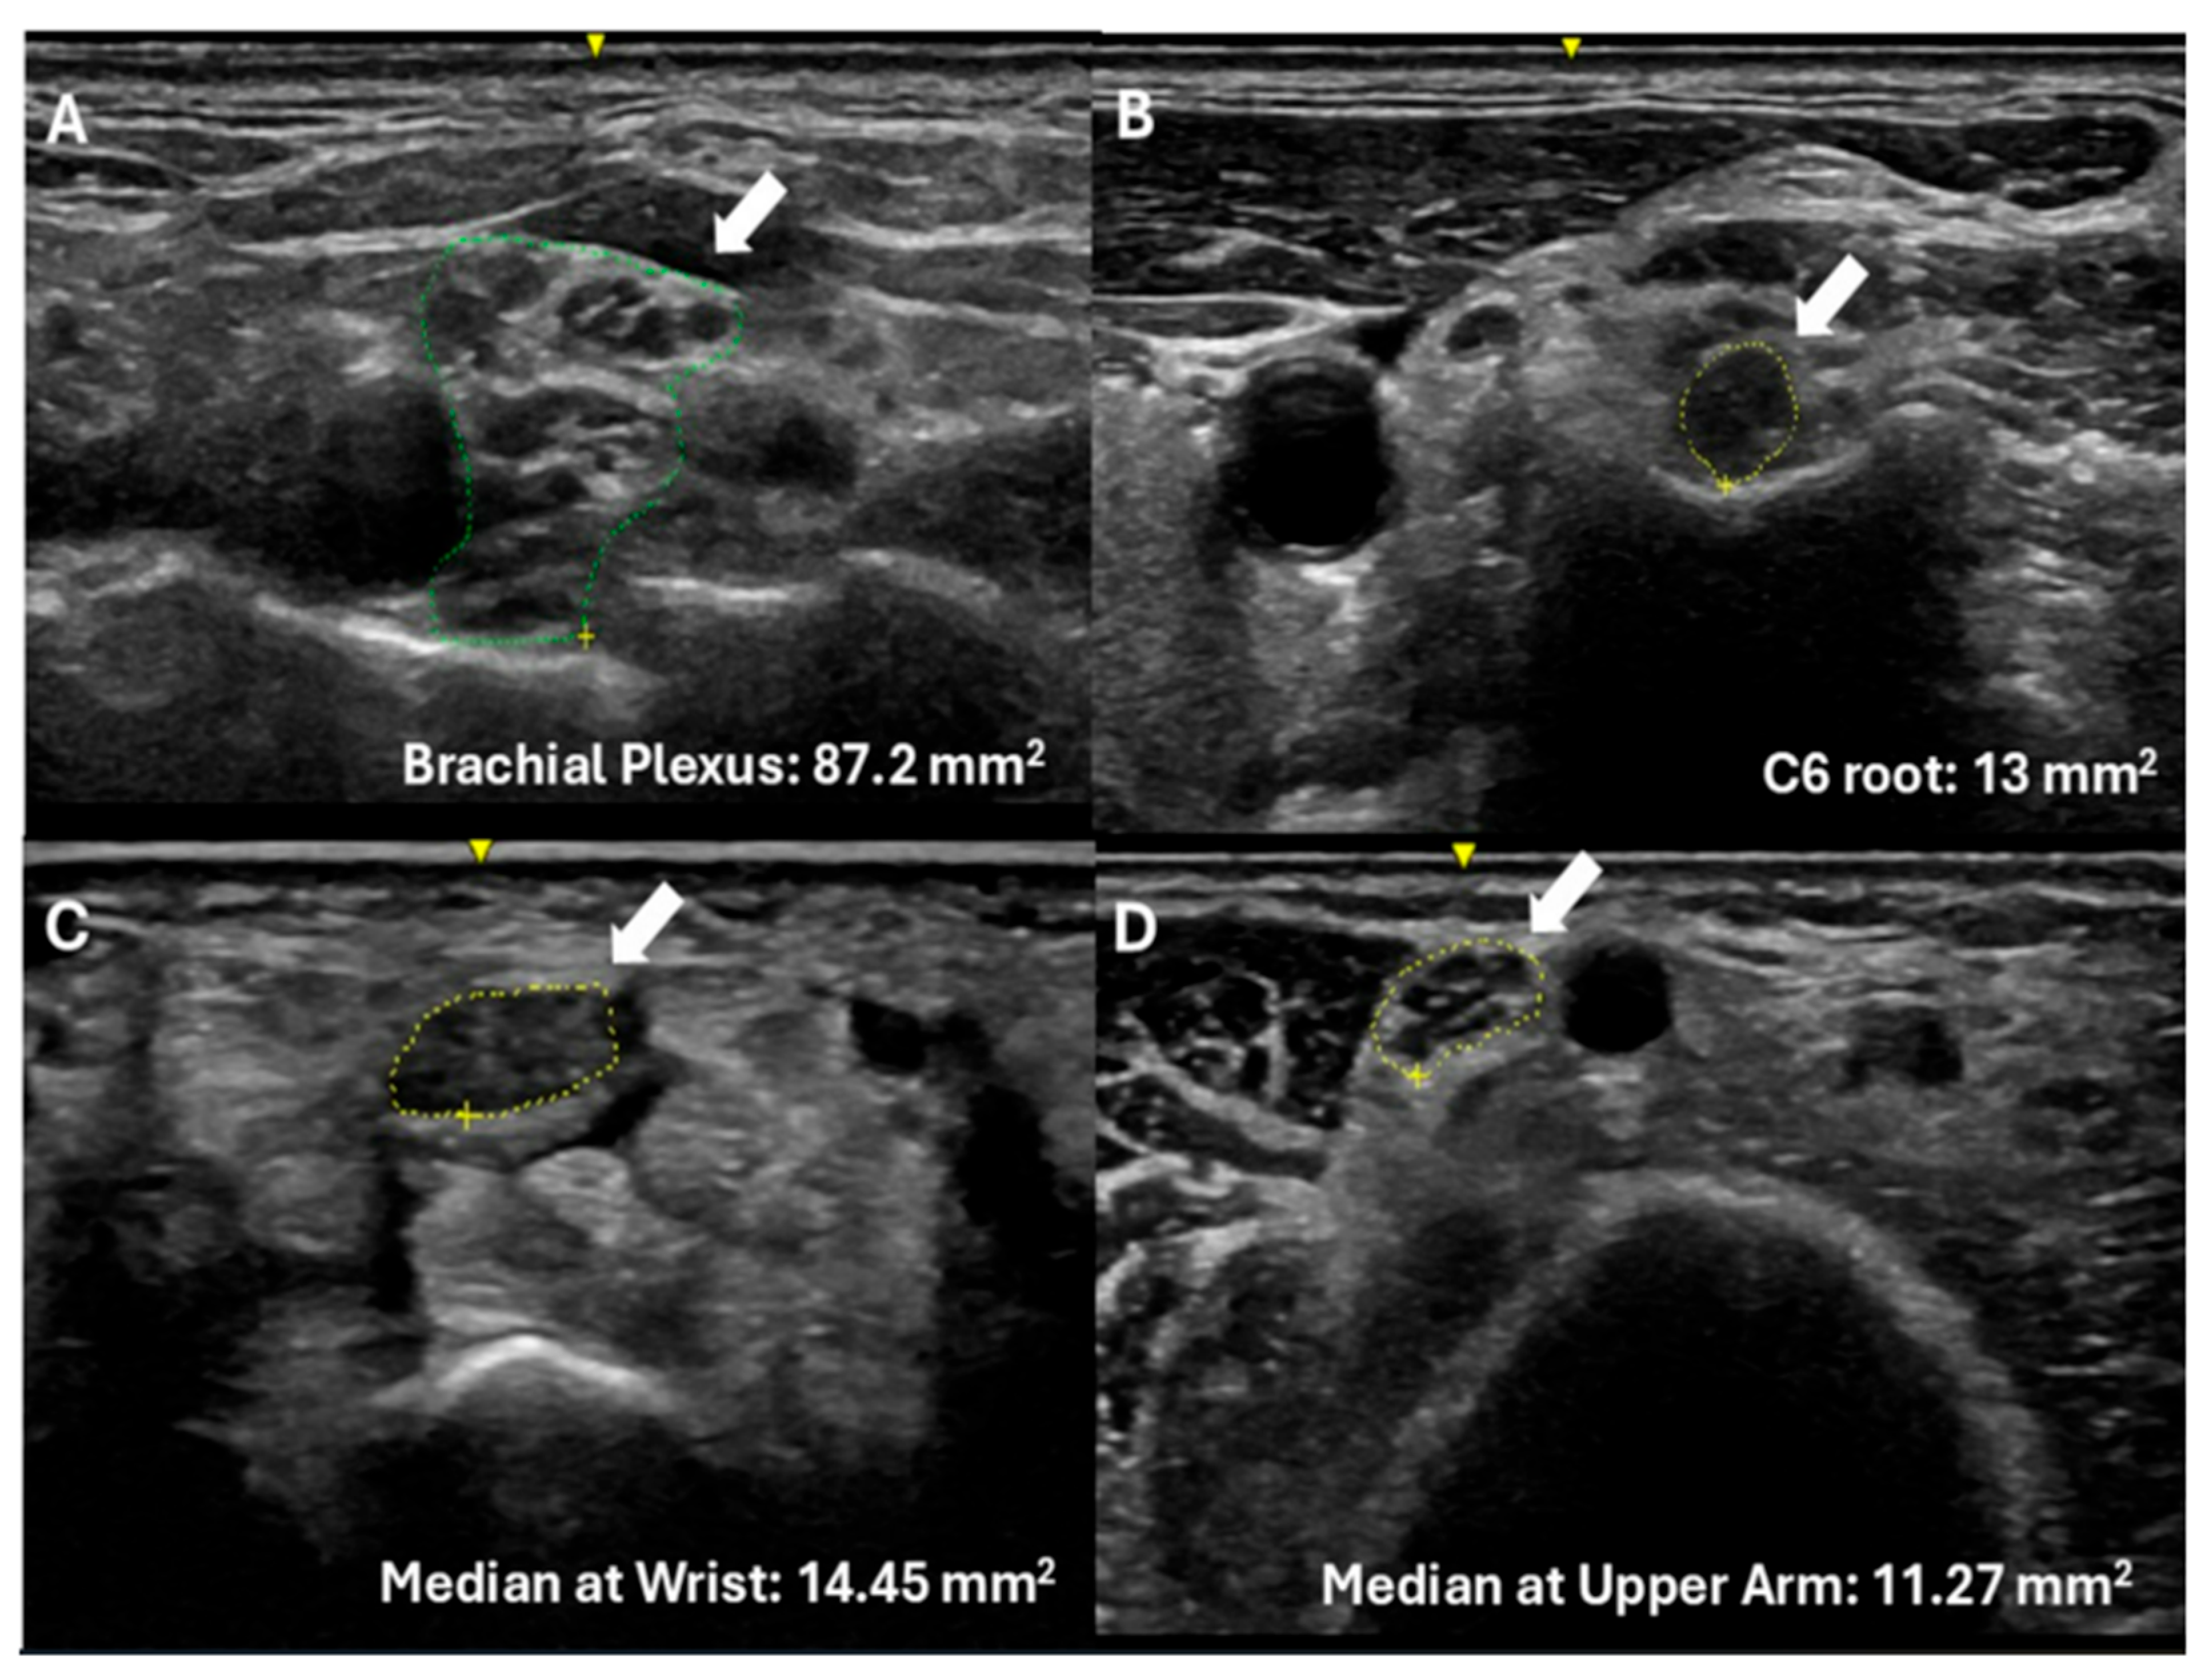

| Site | n | ATTRv-PN CSA | Ref CSA | p Value |

|---|---|---|---|---|

| Median Nerve at the wrist | 31 | 10.17 (2.95) | 8.3 | 0.0075 |

| Median Nerve at the forearm | 31 | 6.85 (2.84) | 6.4 | 0.9064 |

| Median Nerve at the arm | 12 | 9.8 (1.8) | 8.3 | 0.0239 |

| C6 root | 12 | 8.55 (1.38) | 5.8 | 0.0001 |

| Brachial plexus | 12 | 70.82 (18.8) | 46.13 | 0.0001 |

| Site | n | ATTRv-Carriers CSA | Ref CSA | p Value |

| Median Nerve at the wrist | 41 | 10.44 (2.76) | 8.3 | 0.0001 |

| Median Nerve at the forearm | 41 | 6.12 (1.19) | 6.4 | 0.139 |

| Median Nerve at the arm | 24 | 8.9 (2.04) | 8.3 | 0.163 |

| C6 root | 24 | 8.42 (2.10) | 5.8 | 0.0001 |

| Brachial plexus | 24 | 61.97 (14.1) | 46.13 | 0.0001 |